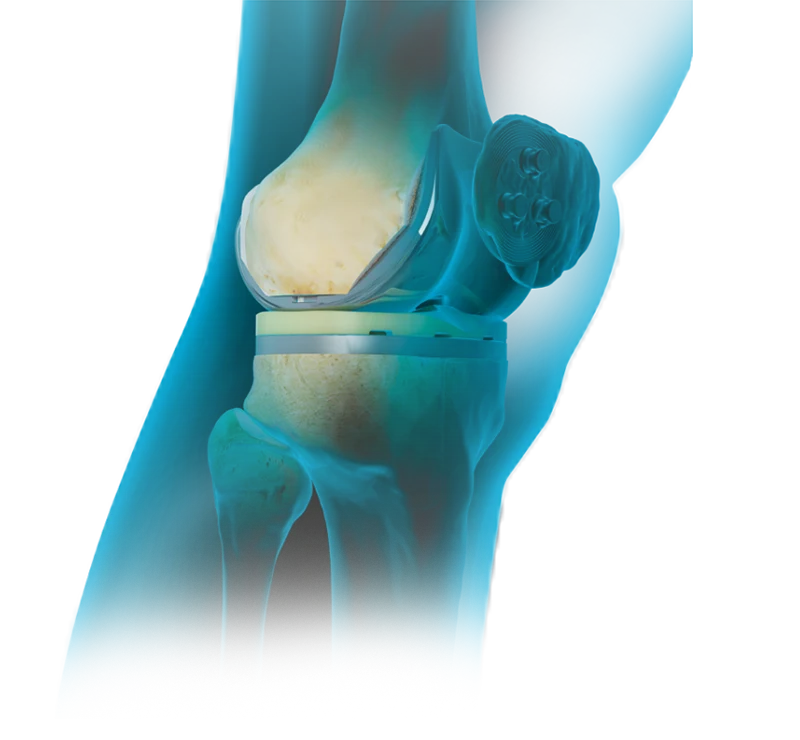

Este procedimento envolve a substituição das superfícies articulares danificadas por próteses artificiais, permitindo alívio da dor e restabelecimento da função articular.

Durante a cirurgia, o cirurgião ortopédico remove a cartilagem danificada e as porções de ossos desgastados do fémur e da tíbia. Em seguida, os componentes protésicos são fixados nas extremidades ósseas, proporcionando uma nova superfície articular lisa e funcional. Dependendo das necessidades individuais do paciente, a patela (ou rótula) também pode ser substituída por um componente protésico.

A substituição protésica do joelho pode ser total ou parcial (frequentemente denominada de artroplastia unicompartimental).

Artroplastia total do joelho é uma solução mais abrangente, envolvendo a substituição de todas as superfícies articulares do joelho (fémur, tíbia e patela) por componentes protésicos, normalmente indicada para pacientes com artrose avançada e com afeção global da articulação do joelho.

Já a artroplastia unicompartimental do joelho, traduz-se na substituição parcial da articulação, quando a artrose se limita a apenas um compartimento do joelho (interno, externo ou anterior), preservando a restante articulação; por ser limitada apenas a uma parte da articulação, é possível obter uma recuperação mais rápida e manter uma sensação mais natural na mobilidade da articulação.